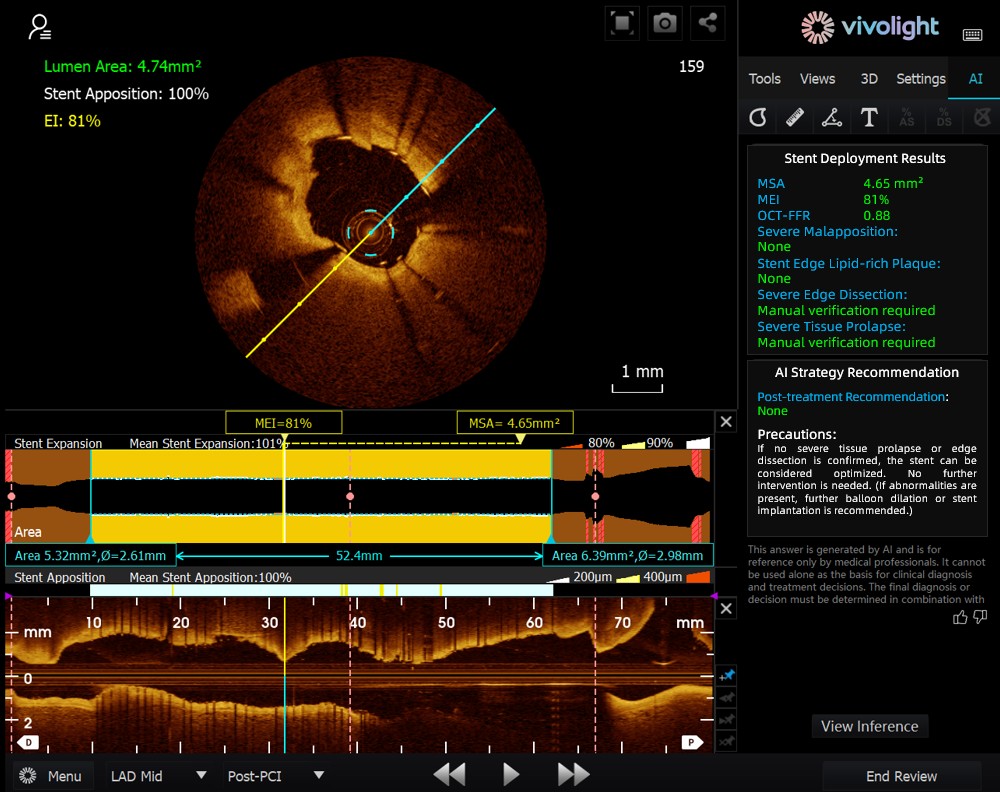

Das auf dem OCT-System von Vivolight Medical basierende AI-OCT ist ein intelligentes Entscheidungsunterstützungssystem der nächsten Generation für die intravaskuläre Bildgebung. Es integriert verstreute intravaskuläre Bildgebungsdaten – darunter Lumendurchmesser, ursächliche Läsionen, OCT-FFR und Plaquebeschaffenheit – in umfassende Behandlungsstrategien und umsetzbare Empfehlungen. Als eigenständige Forschungssoftware, die in die OCT-Plattform integriert ist, wird sie in Zusammenarbeit mit verschiedenen Krankenhäusern entwickelt, um kundenspezifische Versionen für spezifische klinische Bedürfnisse zu erstellen.

Auf dem hochkarätigen Forum betonten Experten, dass das KI-OCT-System einen grundlegenden Wandel von der reinen Bildbetrachtung hin zur Erstellung von Behandlungsplänen darstellt. Es begegnet den Herausforderungen der Informationsflut und der komplexen Entscheidungsfindung bei kardialen Interventionen, die traditionell stark auf der Erfahrung des Arztes beruhen. Zu den wichtigsten Vorteilen des Systems zählen:

●Intraoperative Echtzeitführung: Es organisiert diagnostische Informationen dynamisch während der Operation und liefert wichtige Kennzahlen und klinische Empfehlungen.

●Evidenzbasierte Entscheidungsfindung: Alle Vorschläge entsprechen dem Expertenkonsens und den klinischen Leitlinien, wodurch Strenge und Zuverlässigkeit gewährleistet werden.

●Vollständige Rückverfolgbarkeit: Jede Empfehlung wird durch eine dynamische Datenbank mit vollständiger Dokumentation unterstützt, um Transparenz und Sicherheit zu gewährleisten.

●Vollständiger Offline-Betrieb: Die Datenverarbeitung erfolgt lokal, wodurch die Privatsphäre der Patienten gewahrt und die Systemstabilität gewährleistet wird.

Das KI-OCT-System nutzt eine Architektur aus „kleinen Modellen + großen Datenmengen + großen Modellen“: Kleine Modelle ermöglichen eine präzise Bildinterpretation, während große Modelle umfassende klinische Schlussfolgerungen ermöglichen. Durch die Nutzung hochwertiger kardiovaskulärer Datenbanken und der Retrieval-Augmented Generation (RAG)-Technologie bietet es durchgängige Unterstützung von der Läsionsbeurteilung bis zur Entwicklung von Behandlungsstrategien.